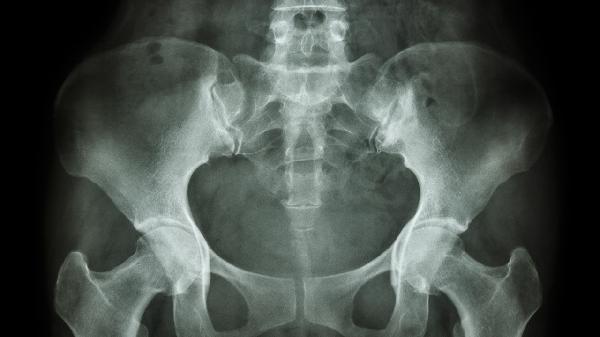

Gardner综合征等遗传性疾病可导致多发性骨瘤,与APC基因突变相关的骨赘生物常累及鼻窦。这类患者往往伴有结肠息肉和软组织肿瘤,需进行全身系统评估。

甲状旁腺功能亢进或维生素D代谢异常可能改变骨重建平衡,促使鼻窦区域出现局限性骨增生。此类骨瘤常伴随血钙磷代谢指标异常,需完善内分泌检查明确病因。